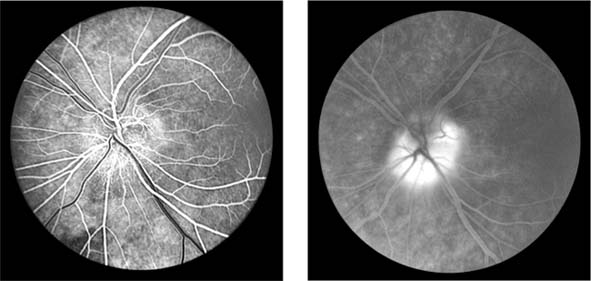

In anterior segment ischemia, patients develop iritis, intraocular pressure changes, and pupillary abnormalities. In retinal ischemia (Figure 15-12A), patients show evidence of capillary dilation and hemorrhages, capillary occlusion, new vessels at the optic disk, and cotton-wool spots.

Figure 15-12

Figure 15-12: A: Fluorescein angiogram of left fundus in a patient with chronic ocular ischemia secondary to Takayasu's disease. Note capillary dilation, leakage of dye, retinal hemorrhages, cotton-wool spots, and neovascularization of the optic nerve head. B: Fluorescein angiogram, showing leakage at optic disk and macula in a patient with chronic ocular ischemia secondary to dural arteriovenous fistula.

Carotid Cavernous Fistula

Carotid cavernous fistula results from a communication between the carotid artery or its branches and the cavernous sinus, producing characteristic vascular signs. Direct carotid fistulas are usually acute, florid, and posttraumatic, whereas fistulas from dural vessels are usually chronic, mild, and not associated with trauma. Clinical features include elevated intraocular pressure, dilated conjunctival vessels, dilated retinal vessels with hemorrhages and fluorescein leakage (Figure 15-12B), ophthalmoplegia (usually lateral rectus), and bruit. computed tomography (CT) and magnetic resonance imaging (MRI) show thickened ocular muscles and a dilated superior ophthalmic vein. The condition must be differentiated from thyroid eye disease, and interventional radiology is the ultimate diagnostic and therapeutic resource.